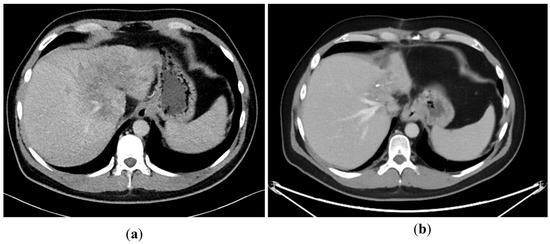

A 43-year-old man went because of persistent fatigue to the general practitioner. The diagnostic showed a large tumor within the central liver (see Figure 1a), which was biopsy-proven as a moderate-differentiated intrahepatic cholangiocarcinoma. An extrahepatic tumor spread could be ruled out (applying an FDG-PET-CT scan, see Figure 2a). Due to the invasion of the hepatic veins, which precluded a primary resection, chemotherapy with cisplatin / gemcitabine was initiated. The tumor showed a partial response (see Figure 1b). We decided to perform surgical exploration with the intent of an ex situ liver resection. Due to an invasion in liver segment VII, even an extended left trisegmentectomy was not possible. We performed an SIRT of both liver lobes resulting in a further, even metabolic (Standardized Uptake Value, SUVmean of the tumor in the initial PET scan: 7.3; SUVmean after treatment: 3.0), response of the tumor (see Figure 2a,b). The CA19-9 levels were always below the reference value. Twenty-two months after the initial diagnosis, the patient could be transplanted with a right living donor lobe from a friend. Histopathologic examination showed an intrahepatic cholangiocarcinoma with a maximum diameter of 6.3 cm. The tumor stage was ypT3, N0, L0, V0, Pn0, R0. Currently, 17 months after the LDLT, the patient is recurrence-free and in good clinical health (see Figure 3). The most recent CA19-9 level is 21.3 U/mL (reference value < 27.0 U/mL).

Figure 2. (a) Tumor in FDG-PET-CT scan at the time of initial presentation. (b) Tumor in FDG-PET-CT scan after chemotherapy and bilobar SIRT.